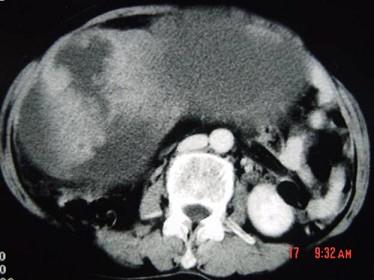

问题 55岁女性患者,腹胀腹痛消瘦一年余,行CT扫描如图所示,你认为最佳答案是 ( )

选项 A、卵巢浆液性囊腺瘤 B、卵巢囊腺癌 C、卵巢囊肿 D、卵巢粘液性囊腺瘤 E、卵巢表皮样囊肿

答案 B